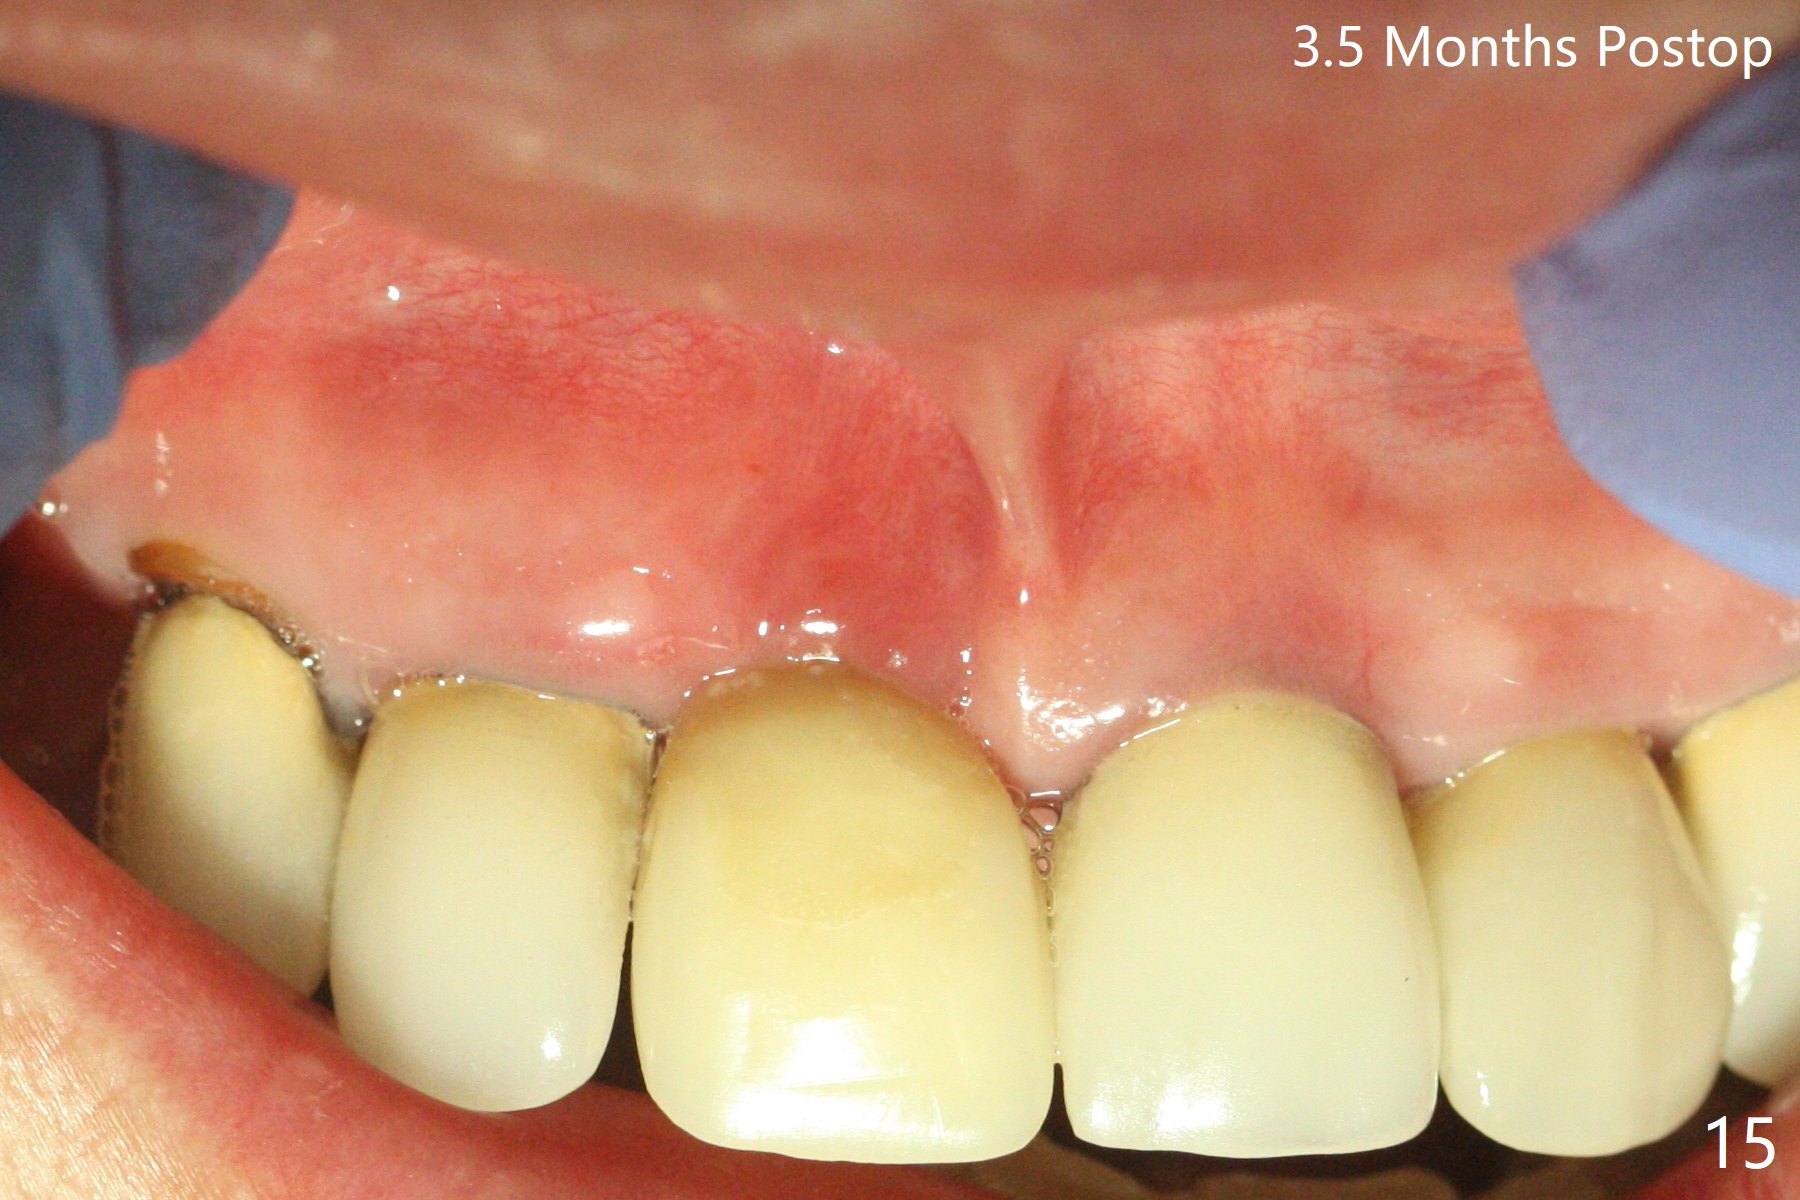

徒手初步钻洞显示方位不对(图一),重新钻洞方位尚可,好像接近鼻底(图二:红线);植入3x11.5毫米一段式植体(图三),3-5个螺纹暴露,植体似乎接近鼻底;旋转植体三趟,植体仿佛卡人鼻底,扭力大约35Ncm,植入粘性骨粉(图四,五:*)前,塞入PRF膜,紧贴颊侧粘膜,促进瘘道愈合。骨粉不仅围绕植体,而且紧贴邻牙牙根(图六(第二轮植骨:overgrafting):<)。病人术后第二周开始使用水牙线,术后三周牙龈健康多了,瘘道消失(图七)。术后六周颊侧骨壁开始塌陷(图八:>),临时牙冠颊侧颈部显得隆起(*)。调整后,牙冠外形改善(图十一至十三),取模前颊侧牙龈缘有可能下降,两个中切牙龈缘可能一致。术后3.5个月骨粉形态(图十四)与术后即刻(图六)有所不同。颊侧牙龈仍红肿轻度触痛(图十五),可能因为临时牙冠不利于局部卫生,所以决定取模制作永久性牙冠。粘固时使用临时胶水,并且涂抗菌素。另外一个可能因素是颊侧骨板薄(图十六:*),细菌感染植体螺纹,永久性牙冠粘固前,拍摄CT(放置cotton roll),必要时,植骨。永久性牙冠远中有缝隙,为了预防病人后悔,使用临时性粘固剂固定(图十七)。Return to No Caries DIO 下一个病例 一段式植体边缘制备 导板与内提升 Xin Wei, DDS, PhD, MS 1st edition 12/22/2020, last revision 06/15/2021